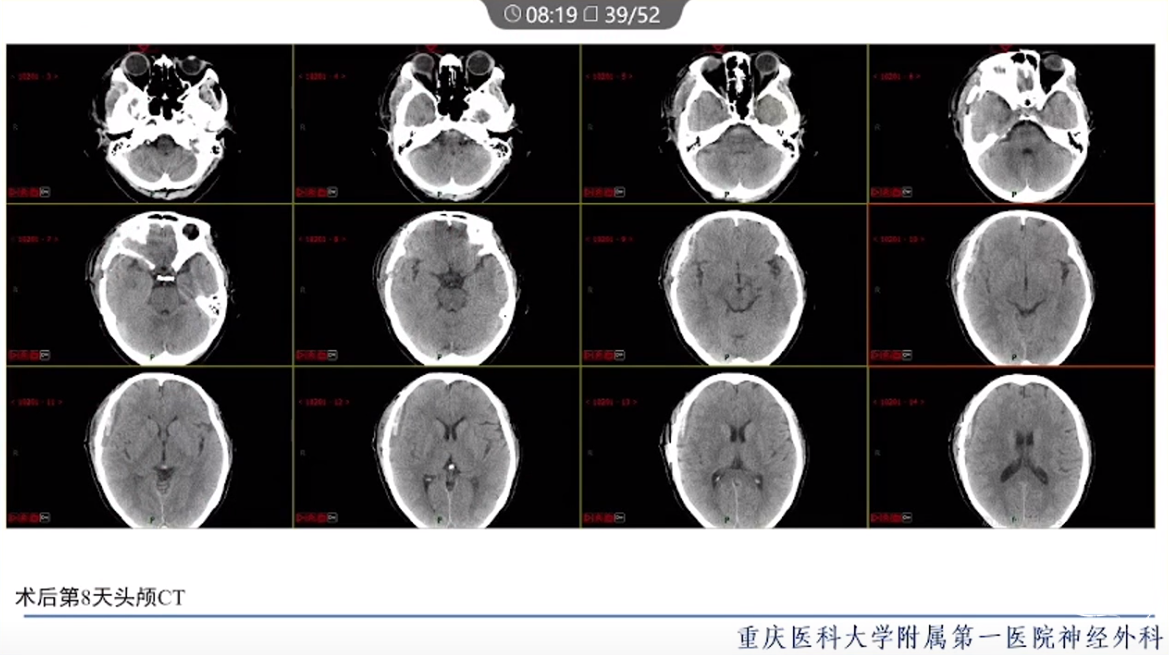

·颈内动脉颈段动脉瘤治疗方式有血管内治疗、外科手术和保守治疗。

·血管内治疗是最常见的治疗方式,随着血管内介入技术的发展和材料的进步,越来越多的动脉瘤可以通过血管内途径治疗。

·对于血管扭曲、血管直径大以及存在抗血小板禁忌的动脉瘤患者,特别是对于颈段大型或巨大型动脉瘤的治疗,常需要外科手术治疗。